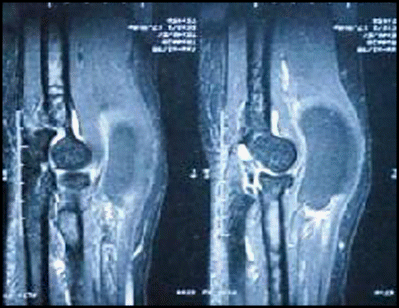

T1 FAT SAT MRI images, showing an intramuscular mass on the supinator muscle

T1 MRI images, showing an intramuscular mass on the supinator muscle

The diagnosis of PINS is based on clinical history and physical examination and is confirmed by electrophysiological studies. Classically, this syndrome has neither pain nor other sensory symptoms, but there are cases of forearm pain and paralysis of the extensor muscles of the forearm. If there is any suspicion, based on clinical examination, of a mass as the causative factor of PINS, MRI scan is the imaging method of choice for evaluating their presence and extent. In this clinical case, however, the lipoma was located intramuscularly, and there was a palpable mass on the forearm.